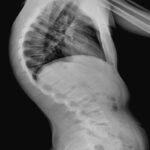

Cifosi da Morbo di Scheuermann: ToracoLombare

Cifosi oltre i 40°

misurata sulle rx in piedi T3 – T12z